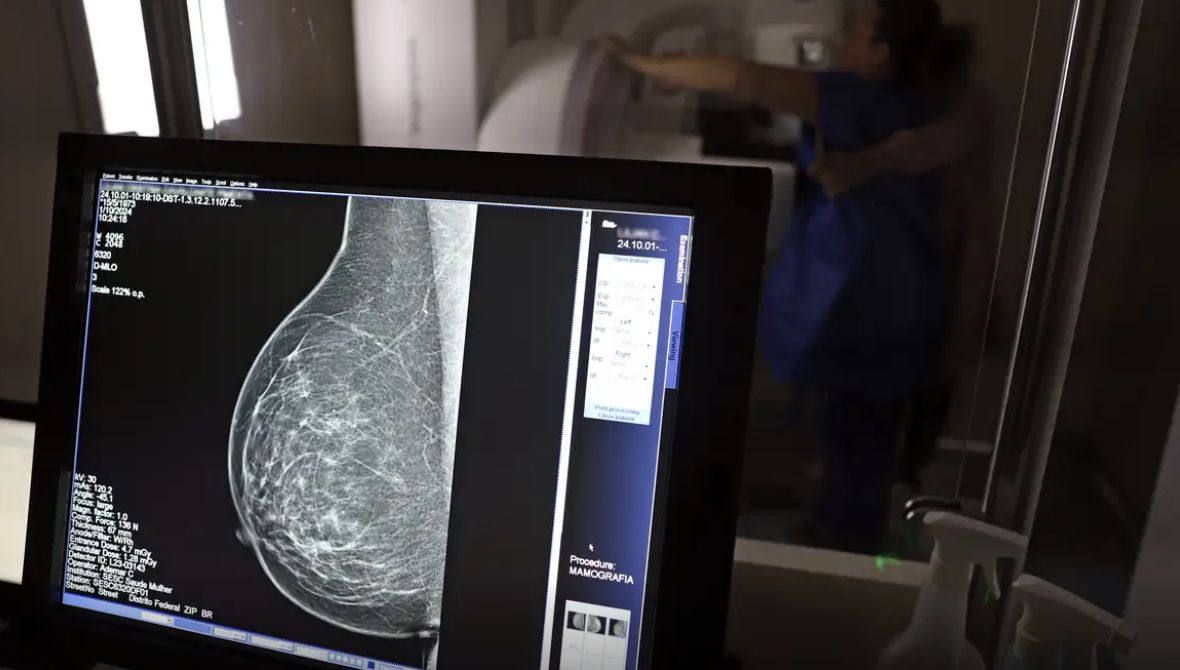

Falta de acesso a mamógrafos limita prevenção do câncer de mama, aponta relatório

O país tem 6.826 equipamentos registrados, sendo 96% em funcionamento.

No mês de conscientização sobre o câncer de mama, um relatório destaca a importância de acesso igualitário ao rastreamento e tratamento da doença. Segundo o Atlas da Radiologia no Brasil, do Colégio Brasileiro de Radiologia e Diagnóstico por Imagem (CBR), o acesso aos mamógrafos ainda é um desafio.

O país tem 6.826 equipamentos registrados, sendo 96% em funcionamento. Metade deles está disponível no Sistema Único de Saúde (SUS), responsável por atender 75% da população. Isso equivale a 2,13 mamógrafos por 100 mil habitantes dependentes do SUS.

Na saúde suplementar, que cobre 25% da população, o cenário é mais favorável: 6,54 aparelhos por 100 mil beneficiárias, quase o triplo da rede pública. O Acre exemplifica essa disparidade — são 35,38 mamógrafos por 100 mil habitantes na rede privada, contra 0,84 no SUS.

Há disparidades regionais. Roraima tem a menor proporção (1,53 por 100 mil), seguida do Ceará (2,23) e Pará (2,25). A Paraíba lidera o ranking (4,32), à frente do Distrito Federal (4,26) e do Rio de Janeiro (3,93).

O Brasil tem uma cobertura muito baixa de mamografias: 24%. O ideal recomendado pela Organização Mundial da Saúde é de 70%. Mesmo em lugares como o estado de São Paulo, que tem a maior concentração de mamógrafos do país, a taxa gira em torno de 26%.

Em setembro, o Ministério da Saúde ampliou as diretrizes de rastreamento, recomendando que mulheres entre 40 e 49 anos realizem mamografias, mesmo sem sintomas. De acordo com o Instituto Nacional do Câncer (Imca), mais de 73 mil mulheres recebem o diagnóstico de câncer de mama anualmente no Brasil.